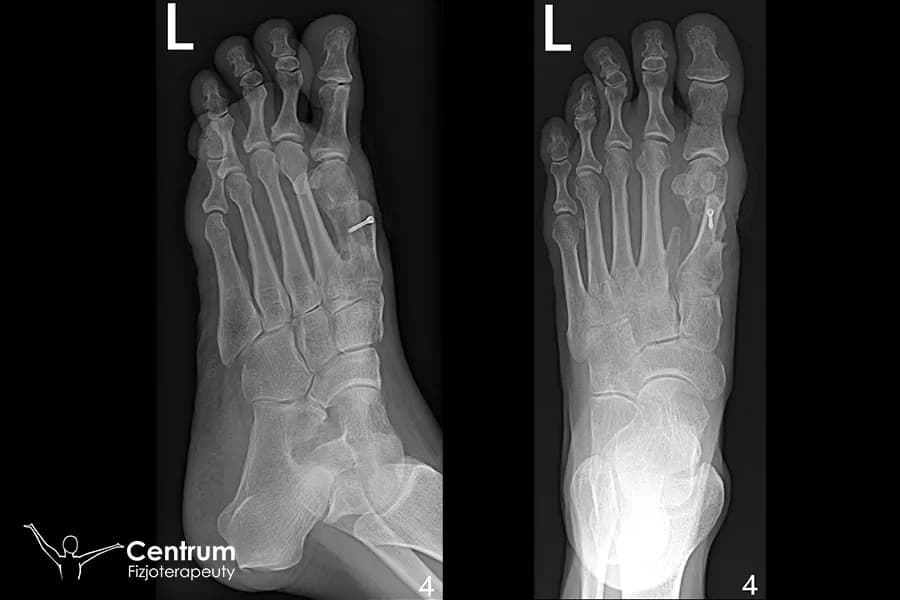

Rehabilitacja nie może rozpocząć się bez zgody lekarza prowadzącego. Zazwyczaj po około 6 tygodniach od operacji odbywa się wizyta kontrolna, podczas której wykonywane jest zdjęcie RTG. To badanie jest kluczowe, ponieważ pozwala lekarzowi ocenić, czy doszło do prawidłowego zrostu kostnego. Dopiero po potwierdzeniu tego faktu i uzyskaniu "zielonego światła" możesz bezpiecznie rozpocząć ćwiczenia rehabilitacyjne. Nie próbuj przyspieszać tego etapu na własną rękę, ponieważ mogłoby to zagrozić efektom operacji.